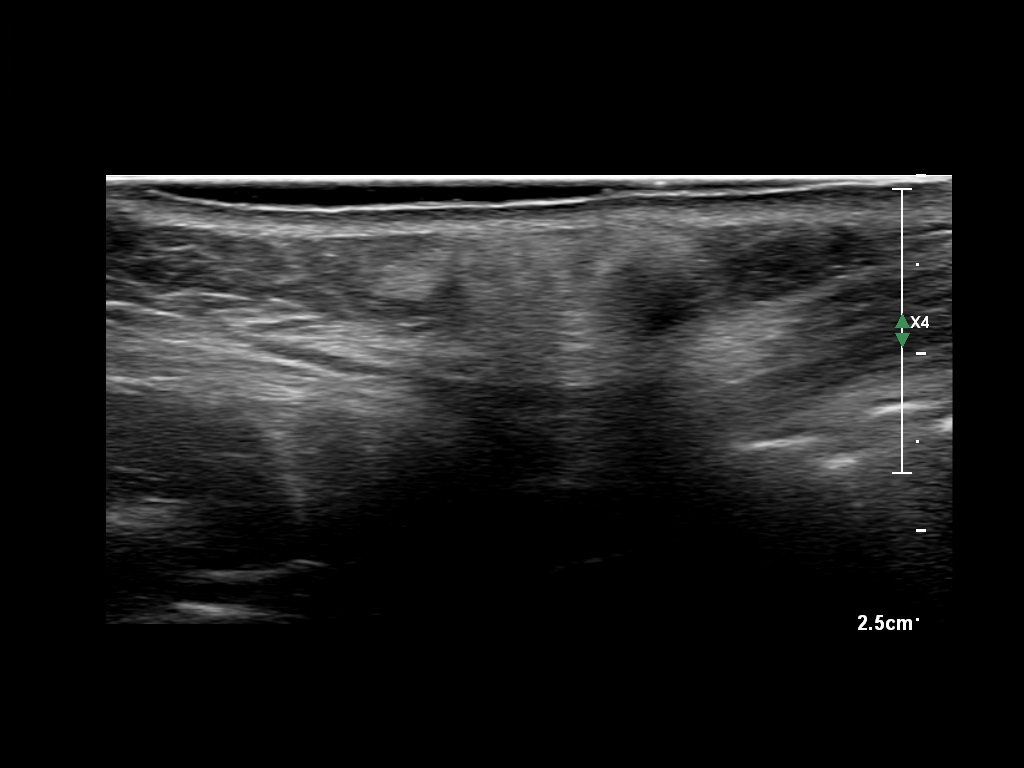

Draw in the second image below where the fillers are located. To check if your answer is correct, swipe the first image to the right.